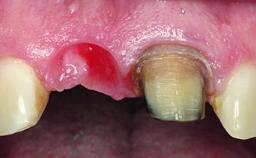

A 36-year-old male patient with a compromised maxillary central incisor was referred by his general dentist for consultation. The patient’s chief complaints were the gradual debonding of a temporary crown on the right central incisor and unsatisfactory esthetics due to an increasing diastema between the right central and lateral incisors. The patient reported a traumatic event some years previously, when a crown had been placed after root-canal treatment. The referring dentist wanted to provide a new crown restoration, but was concerned about the condition of the residual root. Anamnesis was negative for any other dental or periodontal pathology in the remaining dentition. The patient reported taking no medications: He was a smoker (10 to 15 cigs/day) and had realistic esthetic expectations.

Soft Tissue Anatomy Intact Defective

Bone Volume Horizontally and vertically sufficient Horizontally deficient Deficient vertically or deficient vertically AND horizontally